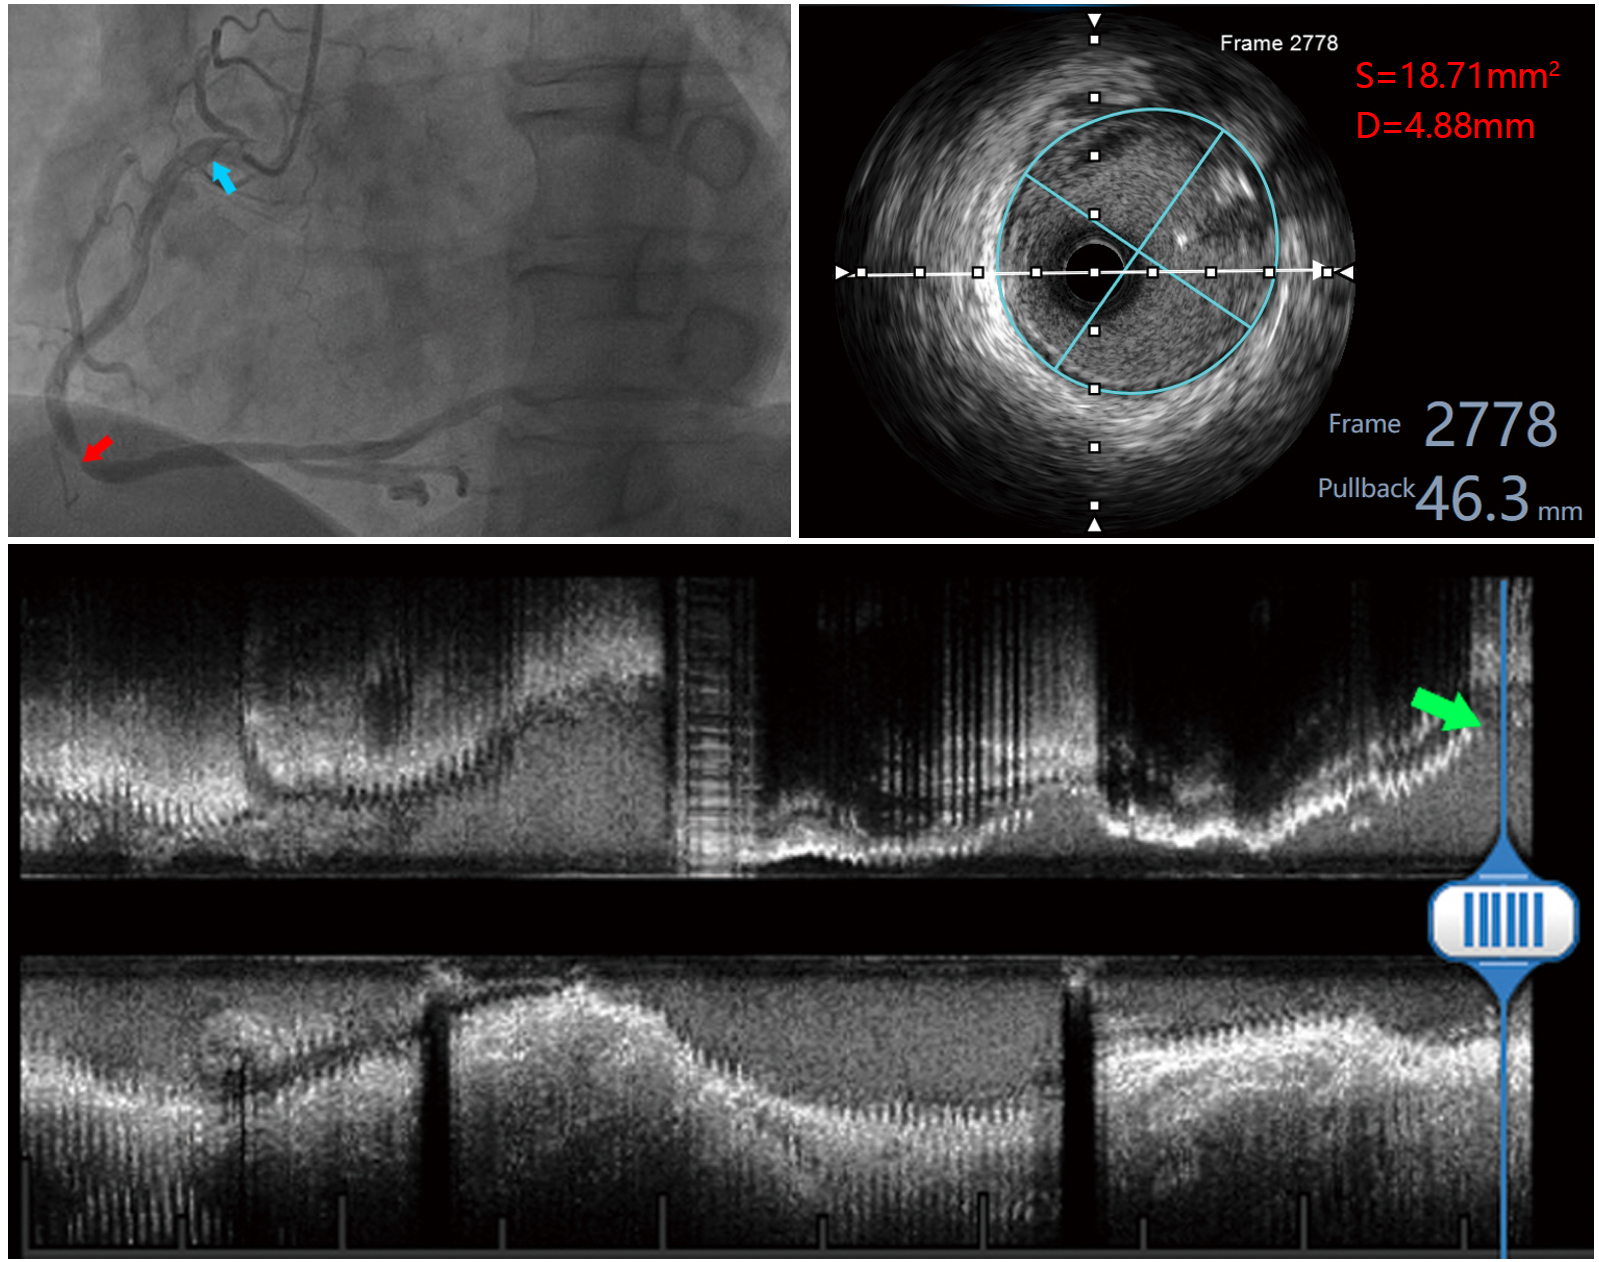

Fig. 2.Measured images of a patient with a right coronary artery lesion. The red arrow in the upper left panel indicates the right coronary artery lesion, and the blue arrow indicates the measurement site proximal to the right coronary; the upper right panel shows the measured area and diameter within the EEM of the proximal right coronary; the lower panel shows the long-axis image of the right coronary artery, and the green arrow indicates the measurement site.